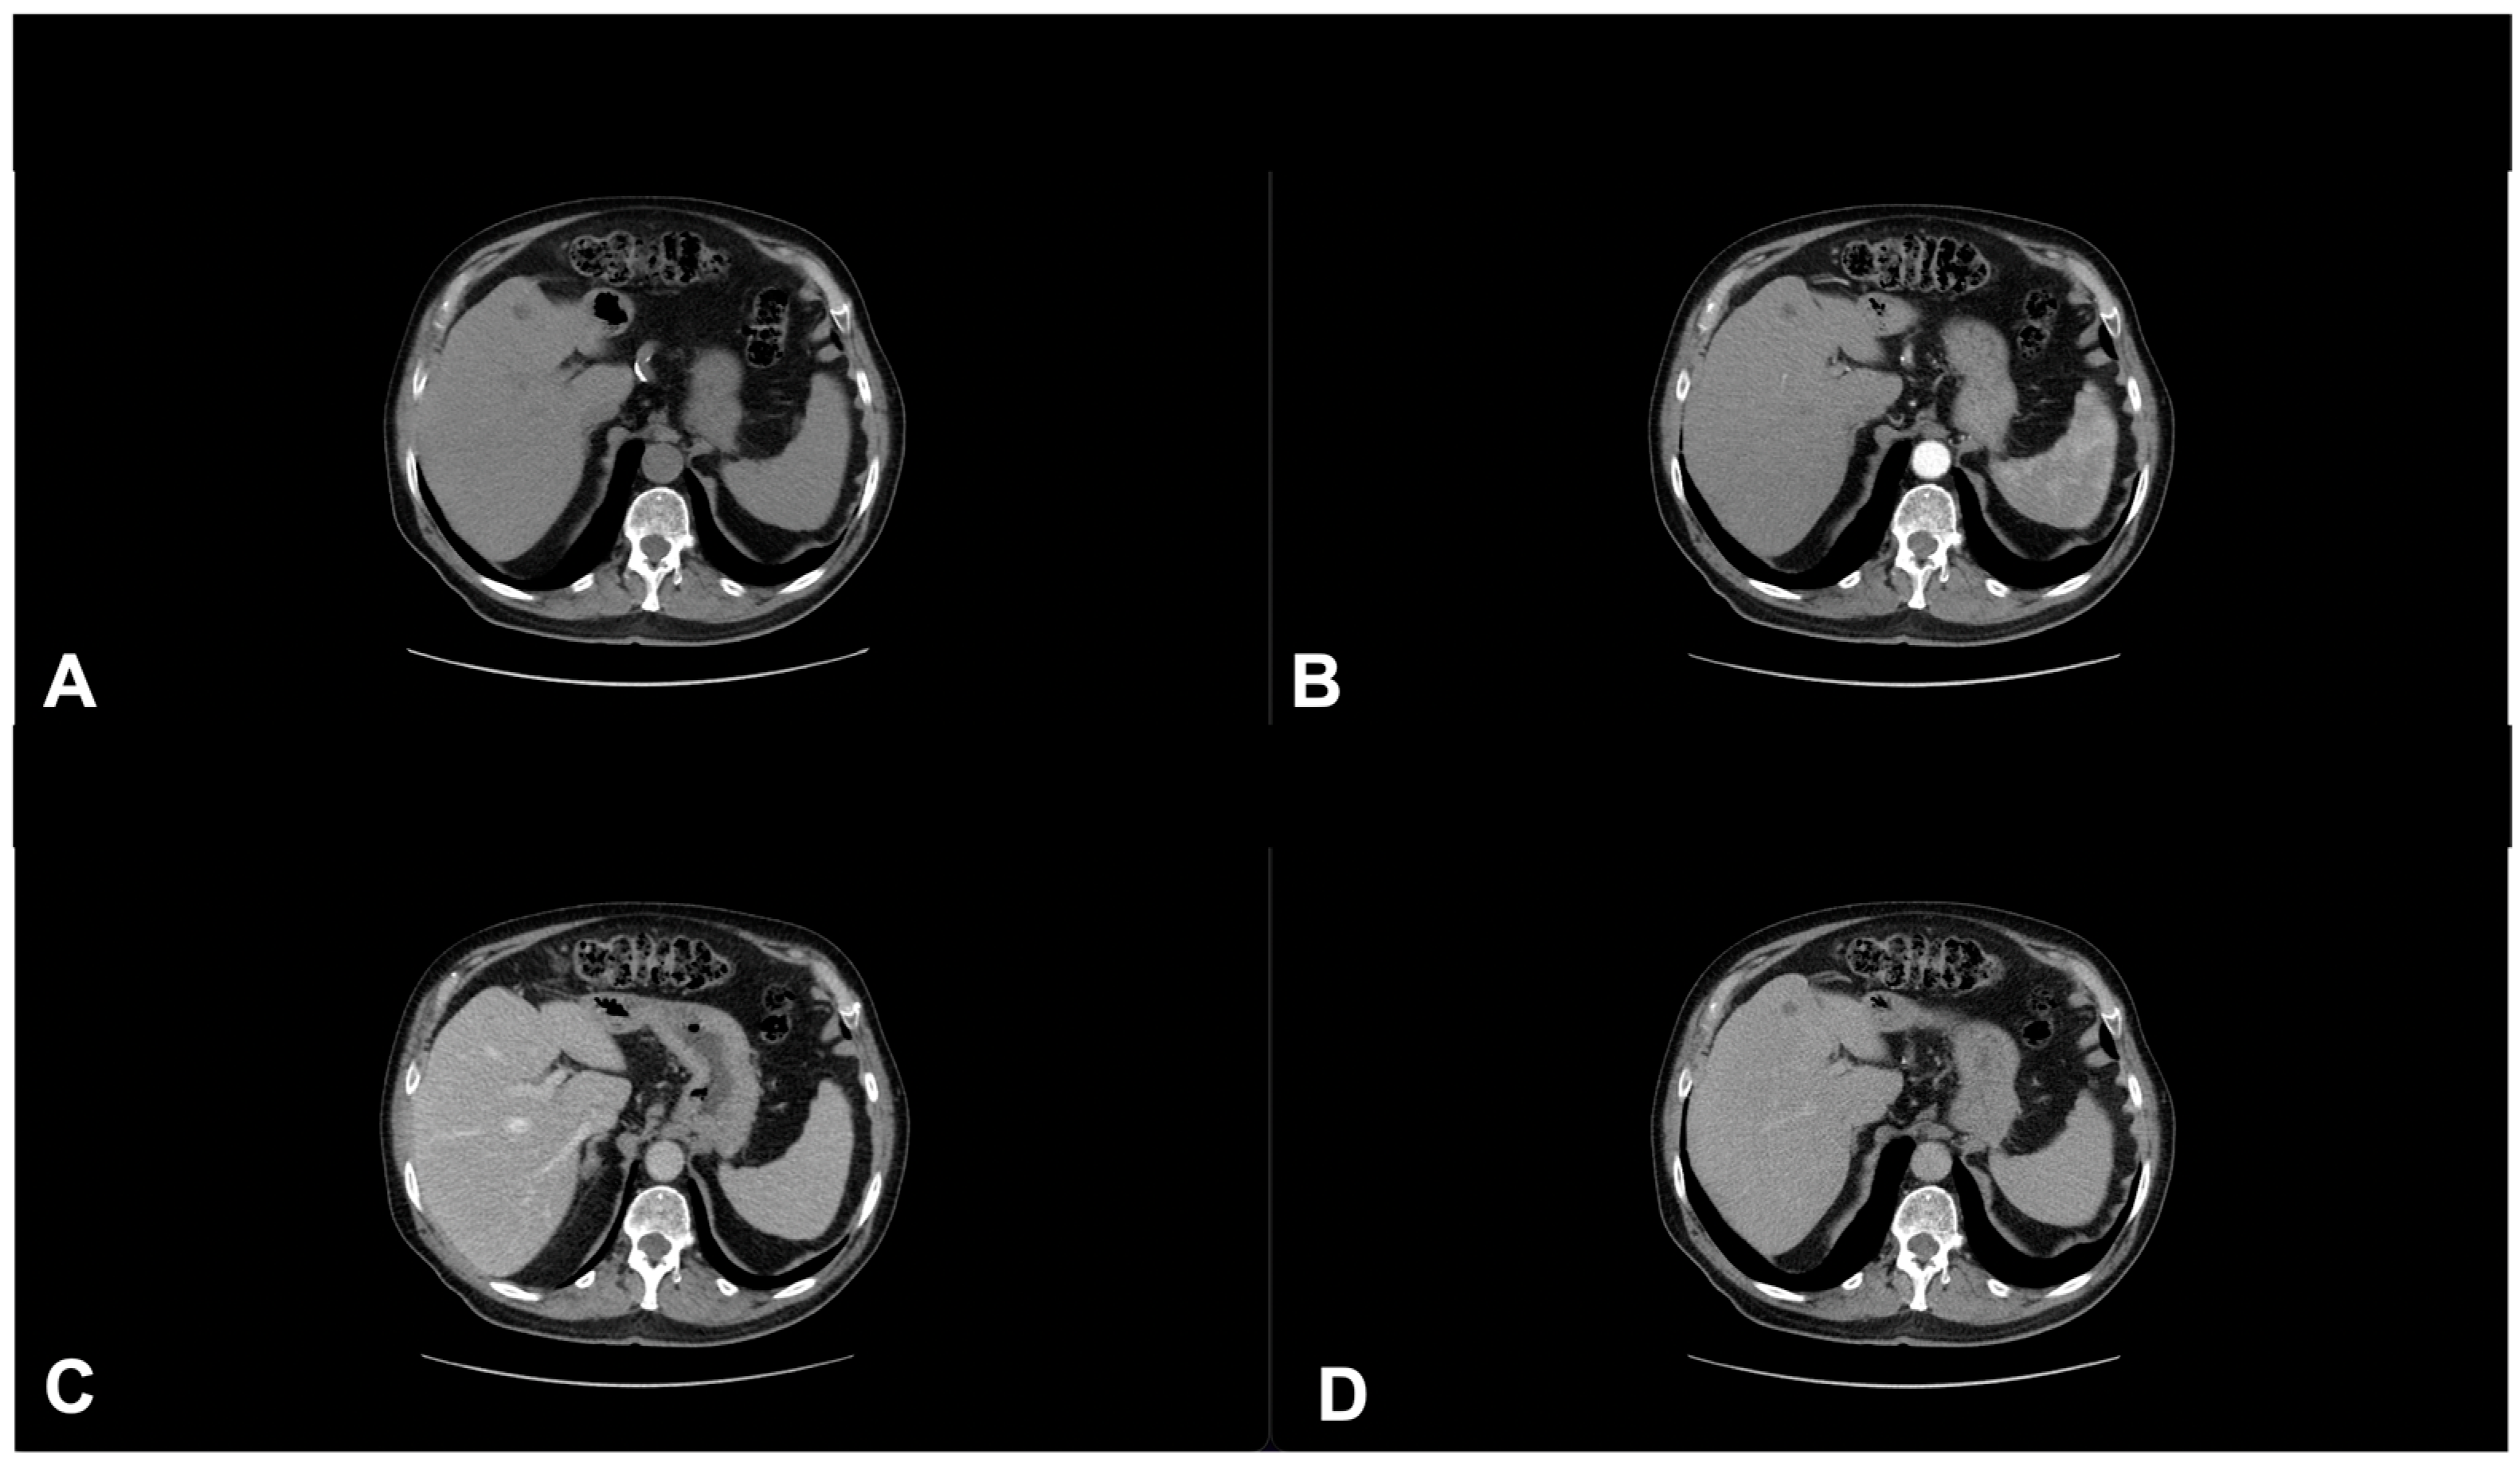

- Granata, V.; Fusco, R.; Piccirillo, M.; Palaia, R.; Petrillo, A.; Lastoria, S.; Izzo, F. Electrochemotherapy in locally advanced pancreatic cancer: Preliminary results. Int. J. Surg. 2015, 18, 230–236. [Google Scholar] [CrossRef] [PubMed]

- Granata, V.; Fusco, R.; Setola, S.V.; Piccirillo, M.; Leongito, M.; Palaia, R.; Granata, F.; Lastoria, S.; Izzo, F.; Petrillo, A. Early radiological assessment of locally advanced pancreatic cancer treated with electrochemotherapy. World J. Gastroenterol. 2017, 23, 4767–4778. [Google Scholar] [CrossRef] [PubMed]